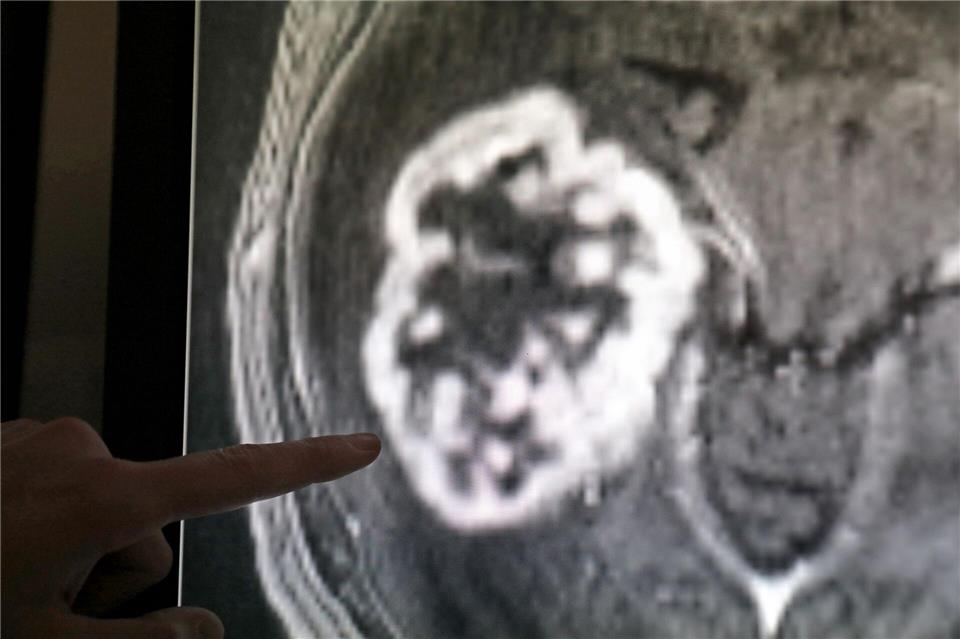

Eine Ärztin soll Brustkrebs-Proben falsch bewertet haben, Patientinnen wurde in der Folge falsch therapiert. Nun ermittelt die Staatsanwaltschaft. Wie die betroffenen Kliniken auf die Fälle reagieren.